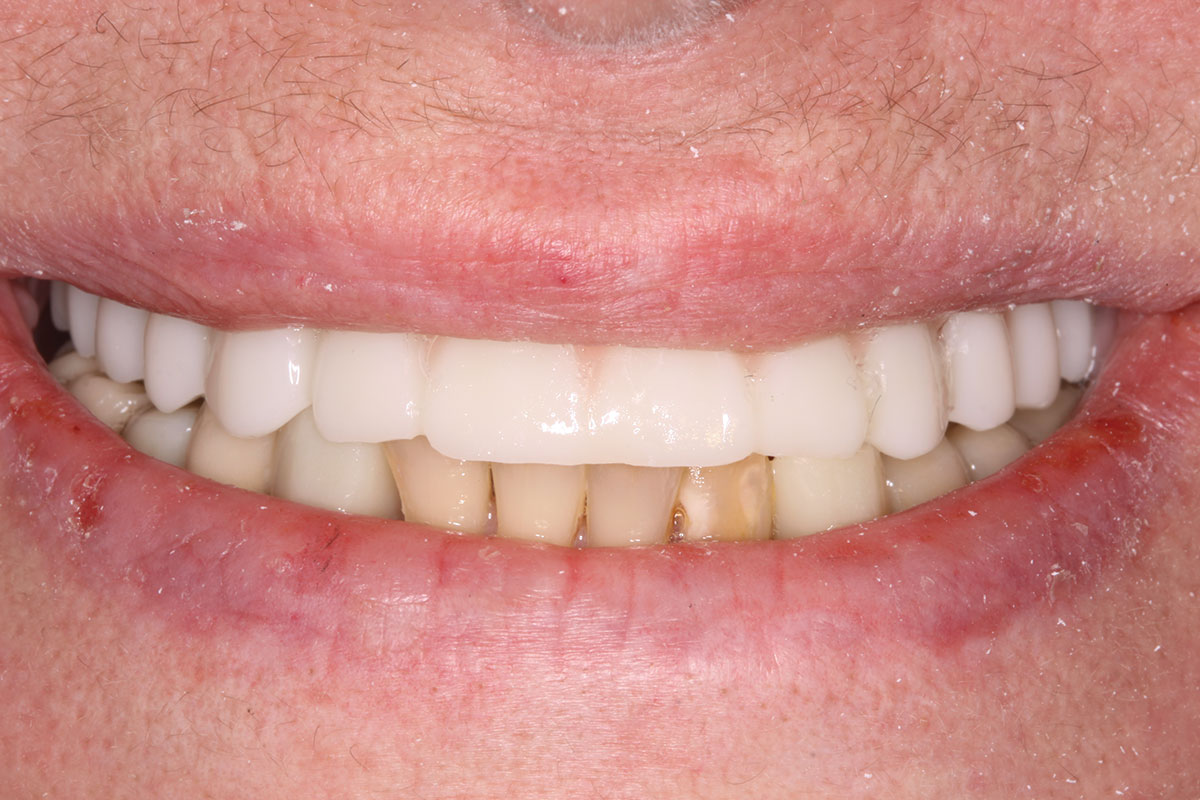

The completed provisional prosthesis was then screwed onto the multi-unit abutments with titanium screws and torqued to 20 Ncm. Screw-access holes were filled, and no occlusal adjustment was necessary. The fit of the prosthesis was precise and stable, and the patient's phonetics were ideal. The patient was overwhelmed by the significant esthetic improvement with this set of teeth in place (Figure 6 through Figure 8).

Fig 7. Maxillary provisional prosthesis seated on implants, on the day of surgery.

Figure 7

Fig 8. Implants and provisional maxillary prosthesis in place, the same day as surgery.

Figure 8